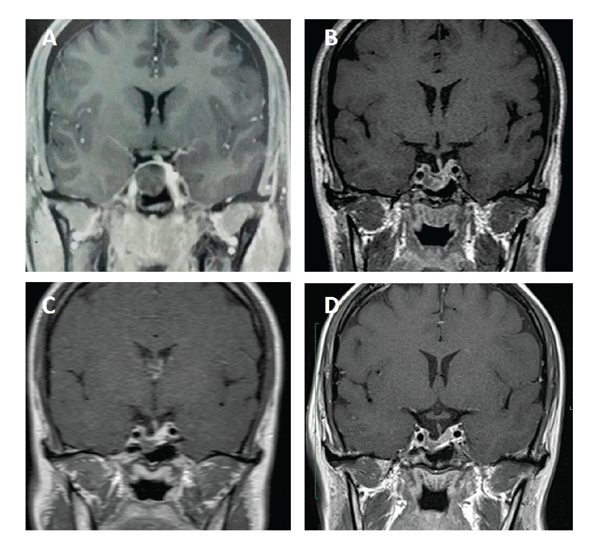

Hormonal evaluation showed elevated baseline and nadir GH on oral glucose tolerance test (53.9 and 34.2 µg/L, respectively) and high IGF-1 (968 µg/L, normal 117-321) (Figure 4). Prolactin, free T4 and cortisol levels were normal. Glucose was 85 mg/dL. MRI depicted a right intra and suprasellar mass with 21×17×19 mm (Figure 5A).

Transsphenoidal surgery was performed, which resulted in partial resection without hormonal remission (GH, 3.84 µg/L and IGF-1, 653 µg/L) (Figure 4). MRI showed a right-sided tumour remnant (Figure 5B). Octreotide 30 mg was reintroduced and after 6 months GH and IGF-1 were 4.9 µg/L and 355 µg/L (normal, 87-238). Cabergoline (up to 2.5 mg/week) was added with partial control (GH, 0.8 µg/L; IGF-1, 334 µg/L) (Figure 4).

The patient was enrolled in a Phase III clinical trial (PAOLA study) evaluating pasireotide long-acting versus long-acting octreotide or lanreotide Autogel in somatostatin analogue-resistant patients.11 At baseline, GH and IGF-1 levels were 3.2 µg/L and 434 µg/L (normal, 115-307), respectively. During the core phase, the patient was assigned to continue treatment with octreotide for 6 months with no change in GH and IGF-1 levels (GH, 3.3 µg/L and IGF-1, 392 µg/L). During the extension phase, the patient was allowed to switch to pasireotide 40 mg as per protocol and after 3 months GH and IGF-1 were normalized (GH, 1.1 µg/L; IGF-1, 151 µg/L). Continued treatment led to a further reduction in IGF-1 levels to below the LLN (80 and 72 µg/L), so pasireotide dose was reduced to 20 mg with normalization of IGF-1 levels (125 and 115 µg/L) (Figure 4). Tumour volume was reduced by approximately 30% during pasireotide treatment (Figure 5D). Before pasireotide treatment, glucose and HbA1c levels were 93 mg/dL and 5.1%, respectively. There was a mild increase in these parameters to 111 mg/dL and 6.2%, respectively, after 6 months of pasireotide treatment. At this time, the patient was oriented with respect to lifestyle changes (diet and exercises) and improved HbA1c to 5.7%.

Figure 5. Sellar gadolinium-enhanced MR coronal images at diagnosis and during treatment with long-acting octreotide and pasireotide in patient 2. (A) at diagnosis; (B) 3 months after surgery; (C) after 9 months of treatment with octreotide and cabergoline; and (D) after 18 months of treatment with pasireotide.